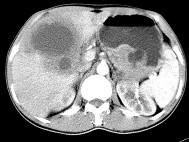

问题 女,61岁,上腹部疼痛1个月,食欲减退,消瘦,CT所见如图,最可能的诊断是()

选项 A.肝脓肿 B.肝转移瘤 C.胃癌肝转移 D.肝包虫病 E.原发性肝癌

答案 C